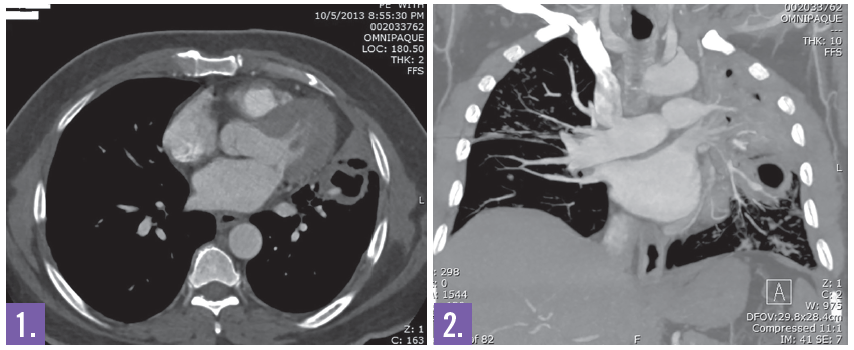

Diagnostic tests. Initial chest x-ray showed interstitial nodular densities and infiltrates throughout both lungs with consolidation, left moderate sized effusion, and decreased left lung volume with left sided mediastinal shift. The chest CT demonstrated a 6.3 cm left upper lobe cavitary lesion (Figures 1 and 2), 3.6 cm left lower lobe cavitary lesion, lingual and anteromedial left lower lobe bronchiectasis, and right upper lobe centrilobular nodules. Sputum was positive for acid-fast bacilli. The patient was diagnosed with active pulmonary tuberculosis (Figure 3).